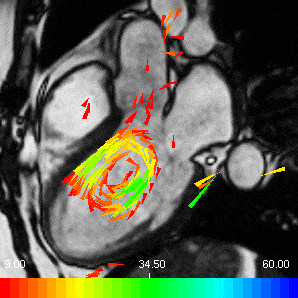

Blood flow in the heart

The heart squeezes the blood into the whole body. At rest, the heart pumps 5 litres of blood per minute. However, at peak exercise, it can pump up to 20 litres of blood per minute!